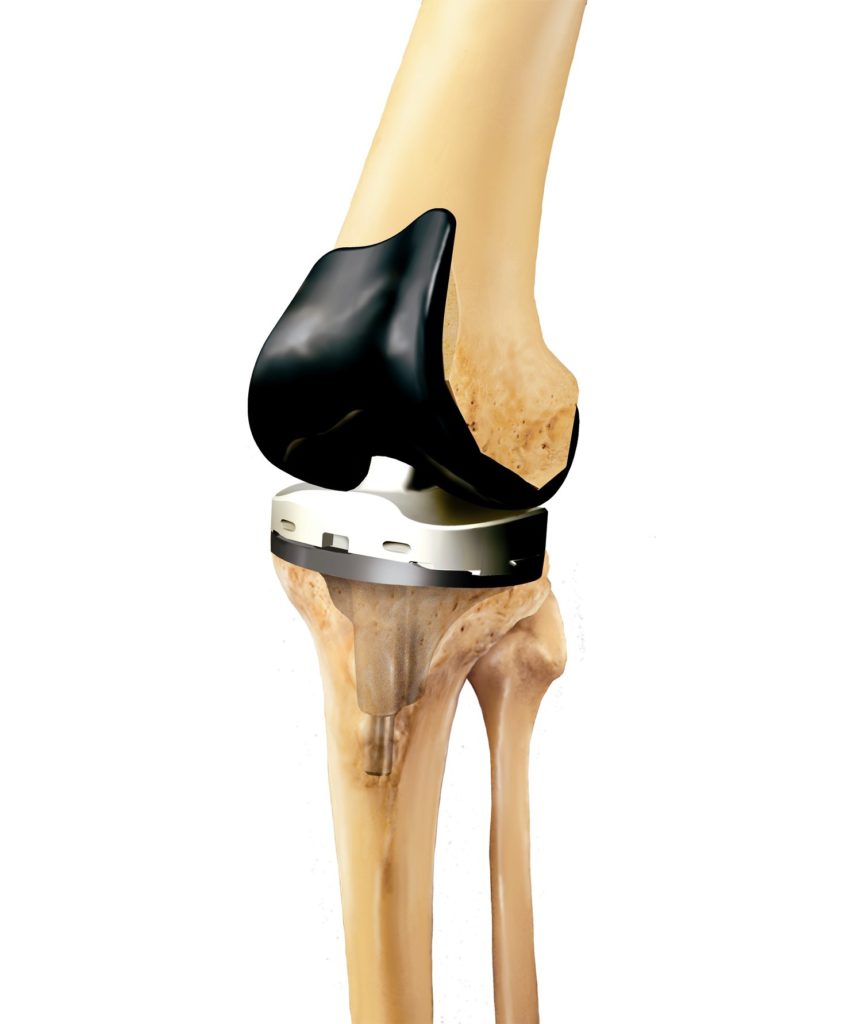

При полном эндопротезировании замене подлежат все три отсека, при частичном – только один из них. Большинство искусственных имплантатов состоят из четырех компонентов:

Частичное и полное эндопротезирование колена.

- Большеберцовый компонент. Плоский элемент, закрепляемый к верхней части голени. Изготавливается в виде металлической платформы с полиэтиленовой (пластиковой) вставкой. Материалом для изготовления — мягкий металл, например, титановый сплав.

- Бедренный компонент – крупная, изогнутая часть имплантата, закрепляемая в бедренной кости. Изготавливается из металла или керамики, чаще из прочных сплавов кобальта и хрома, потому что эта часть участвует в большинстве движений.

- Коленный компонент – куполообразная часть, заменяющая поврежденную коленную чашечку, трущуюся о бедренную кость. Используется не при всех видах суставной хирургии, изготавливается из полиэтилена (прочного пластика).

- Пластиковая прокладка. Располагается между большеберцовой и бедренной частью. Изготавливается из пластика (полиэтилена). Эта гибкая распорка обеспечивает гладкую, скользящую поверхность для обновленного коленного сустава, позволяет ему изгибаться и гнуться.